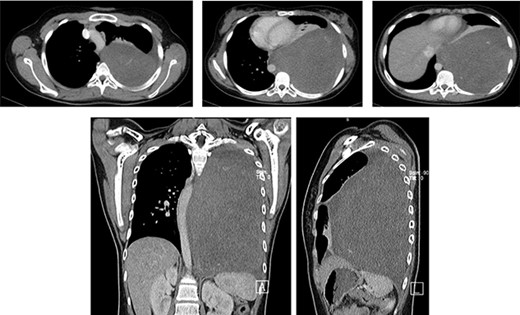

An initial chest radiograph of the patient confirmed tracheal deviation and revealed a mass in the left hemithorax. Chest CT scan (Fig. 1) showed a large mass occupying the entire left posterior hemithorax measuring 12.3 cm (AP) × 14.4 cm (T) × 22.8 cm (CC) with associated partial collapse of the left lung and mediastinal shift to the contralateral side suggestive of pleuropulmonary blastoma vs. neurogenic tumor (ganglioneuroma). This was followed by a CT-guided core needle biopsy which revealed benign spindle cells on a myxoid background. Abdominopelvic ultrasound was normal.

Axial, coronal and sagittal chest CT soft tissue window shows a large mass occupying the entire left posterior hemithorax measuring 12.3 cm (AP) × 14.4 cm (T) × 22.8 cm (CC) with associated partial collapse of the left lung and mediastinal shift to the contralateral side; the mass abuts to the descending aorta. No evidence of rib or thoracic spine destruction seen.